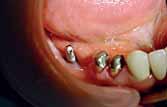

The implant design in this case composed of one abutment connected to the peripheral struts by 4 abutment struts for each implant. One hole was drilled on each implant on a peripheral strut (distal aspect) for the placement of titanium fixation screw. Implants should be thoroughly cleaned and sterilized before placement.

The surgical insertion of the implant is very similar to the direct bone impression surgery but is more rapid and causes less swelling and discomfort to the patient.

After the implant is placed on the ridge a titanium screw is used to fix the implant on the ridge to obtain the primary stability this screw would be of no use after the healing of tissues because the implant would be stable on place by the attachment of the soft tissues to the bone which holds the struts of the implant in between.

The site is then sutured again.

Sutures were removed after 1 week.

After 2 weeks of implant placement the patient came back. A preparation was done to the premolars at both sides and the impression was taken.

4 units bridge was fabricated for each side splinting the implant abutment to the 2 natural teeth of each side.